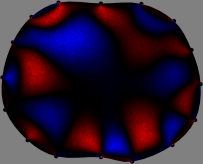

To explain the FER method, we closely examine the correlations among column vectors of the sensitivity matrix 𝕊𝕊\mathbb{S}, described in Fig. 2. The correlation between 𝐒ksubscript𝐒𝑘{\bf S}_{k} and 𝐒subscript𝐒{\bf S}_{\ell} can be expressed as

for i=1,,16𝑖116i=1,\cdots,16[23]. This shows that the column vector 𝐒ksubscript𝐒𝑘{\bf S}_{k} is like an EEG (electroencephalography) data induced by dipole sources with directions uj,j=1,,16formulae-sequencesubscript𝑢𝑗𝑗116\nabla u_{j},j=1,\cdots,16 at locations ΔksubscriptΔ𝑘\Delta_{k}. Given that two dipole sources at distant locations produce mutually independent data, the correlation between 𝐒ksubscript𝐒𝑘\mathbf{S}_{k} and 𝐒subscript𝐒\mathbf{S}_{\ell} decreases with the distance between ΔksubscriptΔ𝑘\Delta_{k} and ΔsubscriptΔ\Delta_{\ell}. Fig. 2 shows a few images of the correlation 𝐒k,𝐒(|𝐒k||𝐒|)1subscript𝐒𝑘subscript𝐒superscriptsubscript𝐒𝑘subscript𝐒1\left\langle\mathbf{S}_{k},\mathbf{S}_{\ell}\right\rangle(|\mathbf{S}_{k}||\mathbf{S}_{\ell}|)^{-1} as a function of \ell for four different positions ΔksubscriptΔ𝑘\Delta_{k}. The correlation decreases rapidly as the distance increases. In the green regions where the correlation is almost zero, 𝐒subscript𝐒{\bf S}_{\ell} is nearly orthogonal to 𝐒ksubscript𝐒𝑘{\bf S}_{k}.